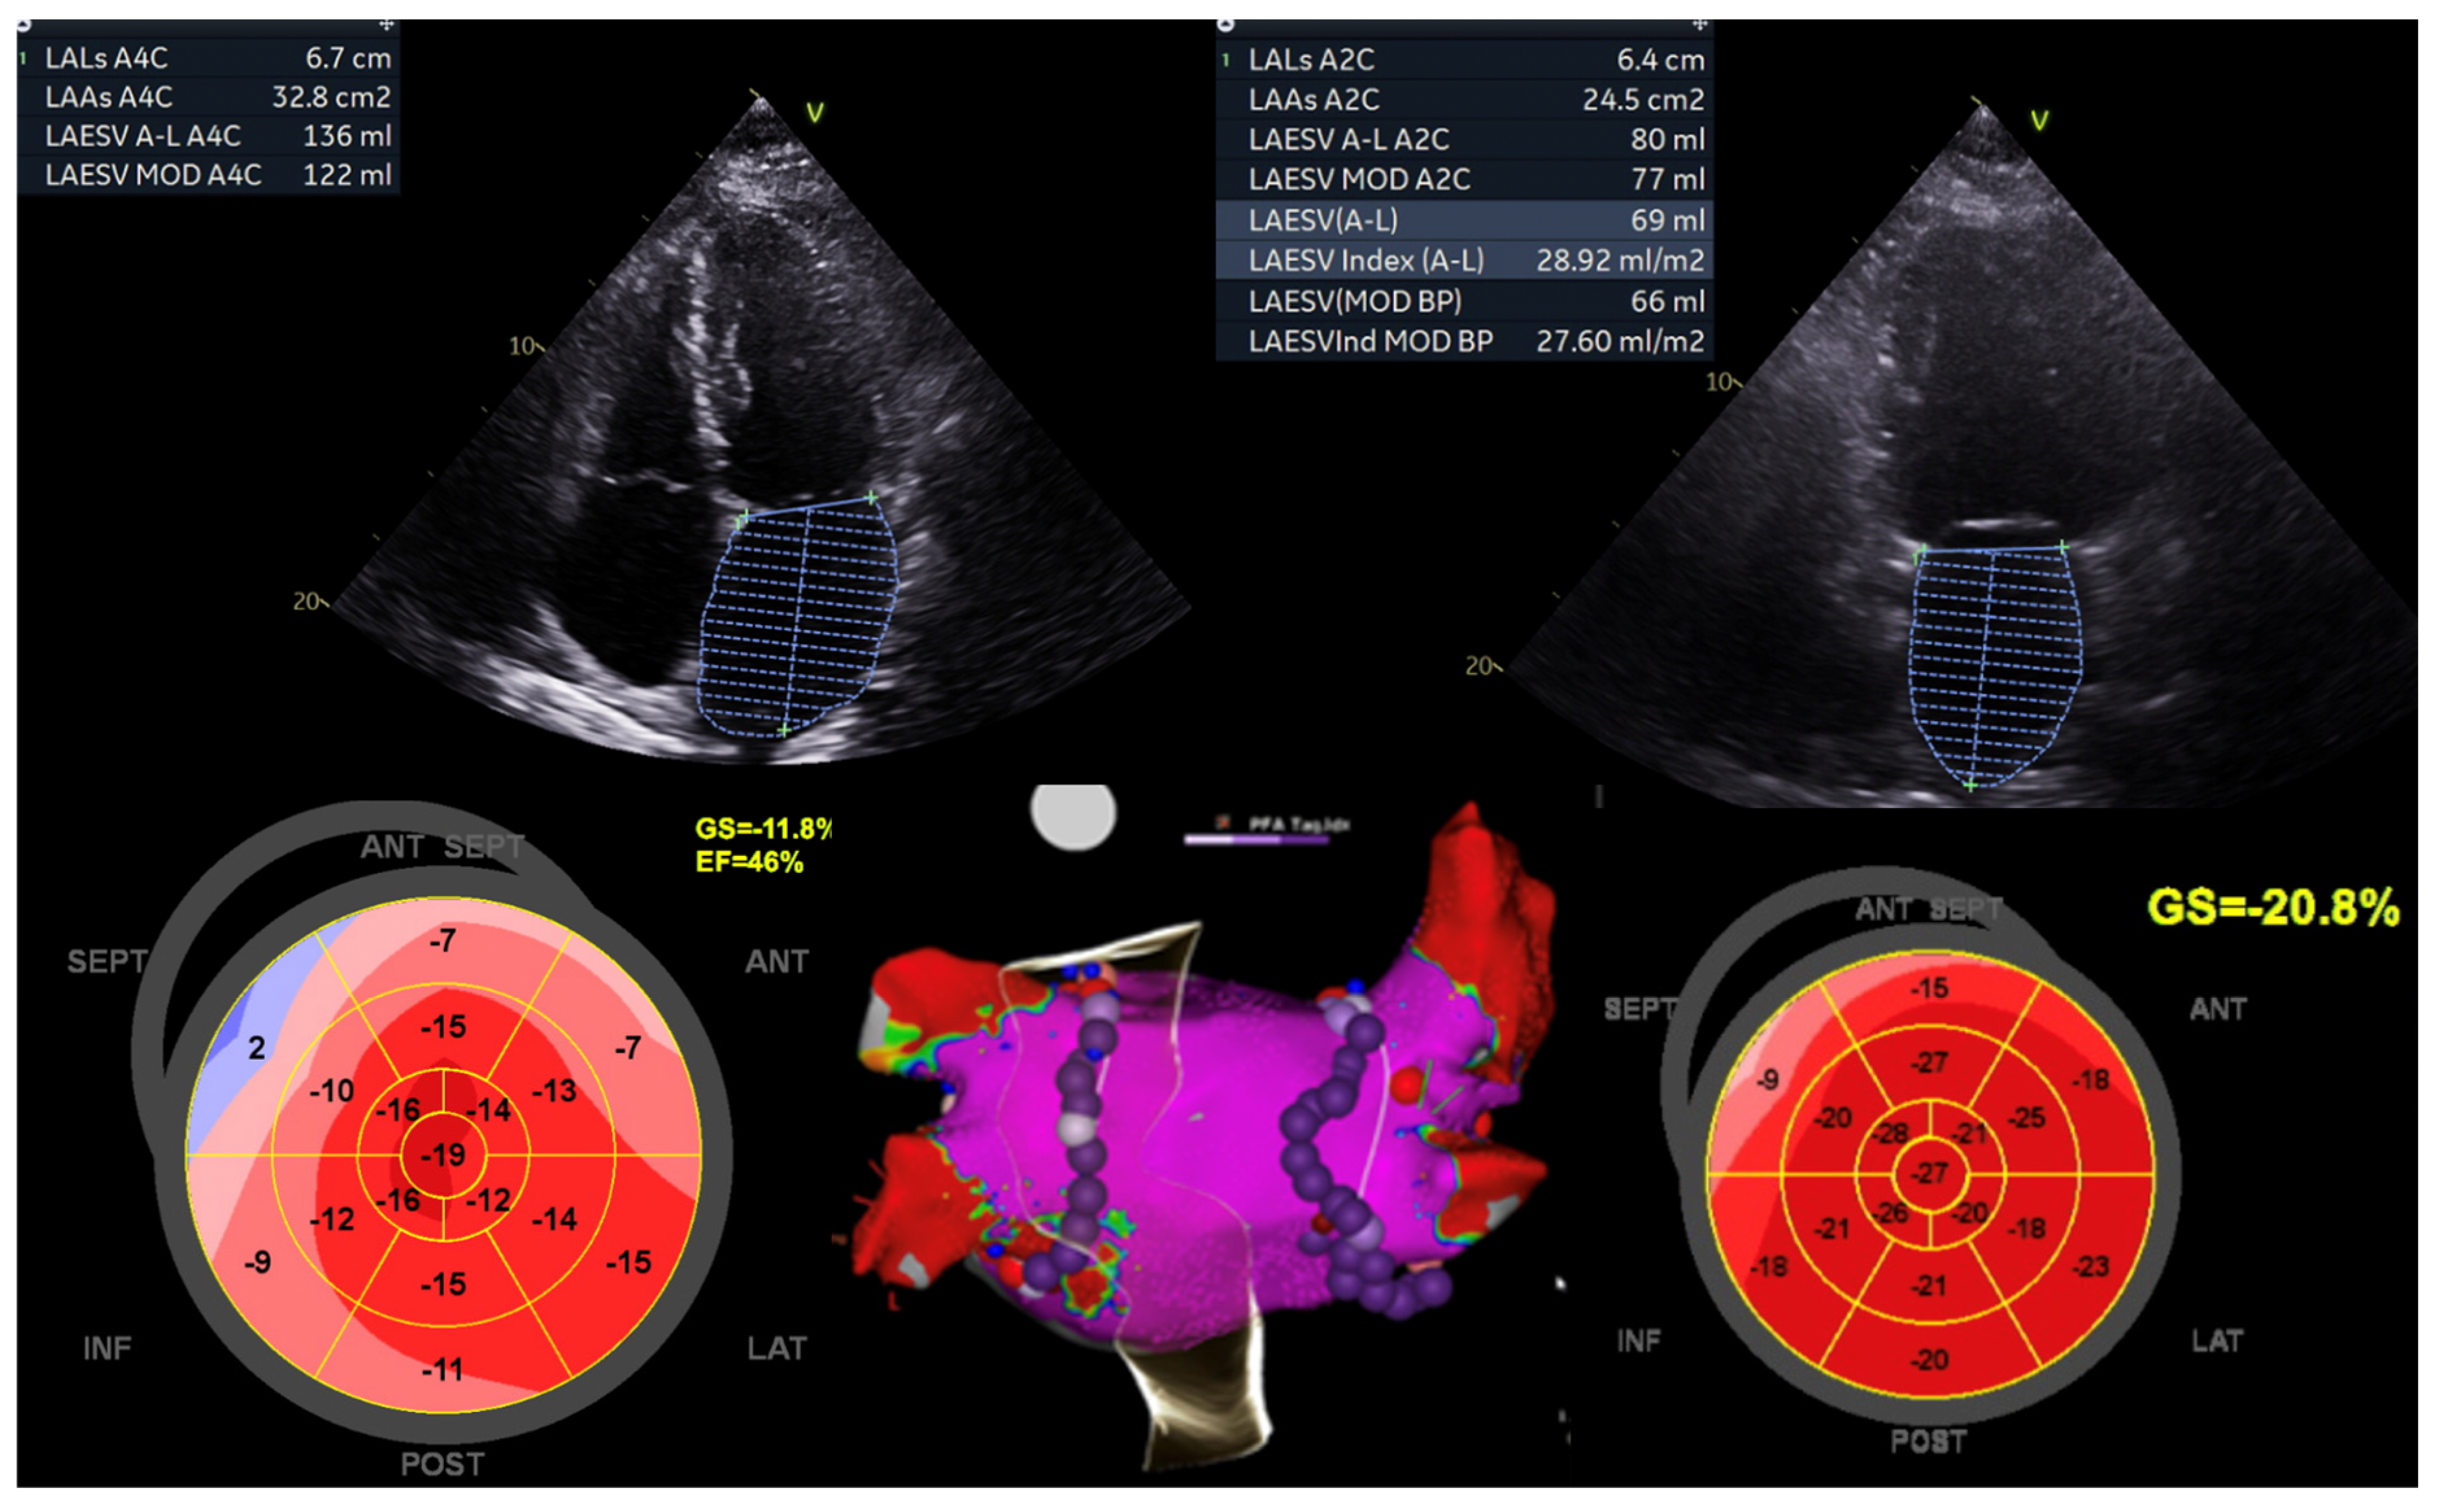

Figure 5. This image emphasises the positive impact of atrial fibrillation (AF) ablation on enhancing outcomes and quality of life for a 64-year-old woman with persistent AF and HFmrEF. Initially, she had a baseline left ventricular ejection fraction (LVEF) of 46%, a left atrial area (LAA) of 32.8 cm2, and a 100% AF burden. Following AF ablation (pulmonary vein isolation), her LVEF percentage significantly increased to 68%, and her LAA reduced to 24.5 cm2 within 3 months, accompanied by an improvement in global longitudinal strain (GLS) from −11.8% to −20.8%. Subsequent Holter monitoring showed no AF recurrence. Image courtesy of the Canberra Heart Rhythm Centre.